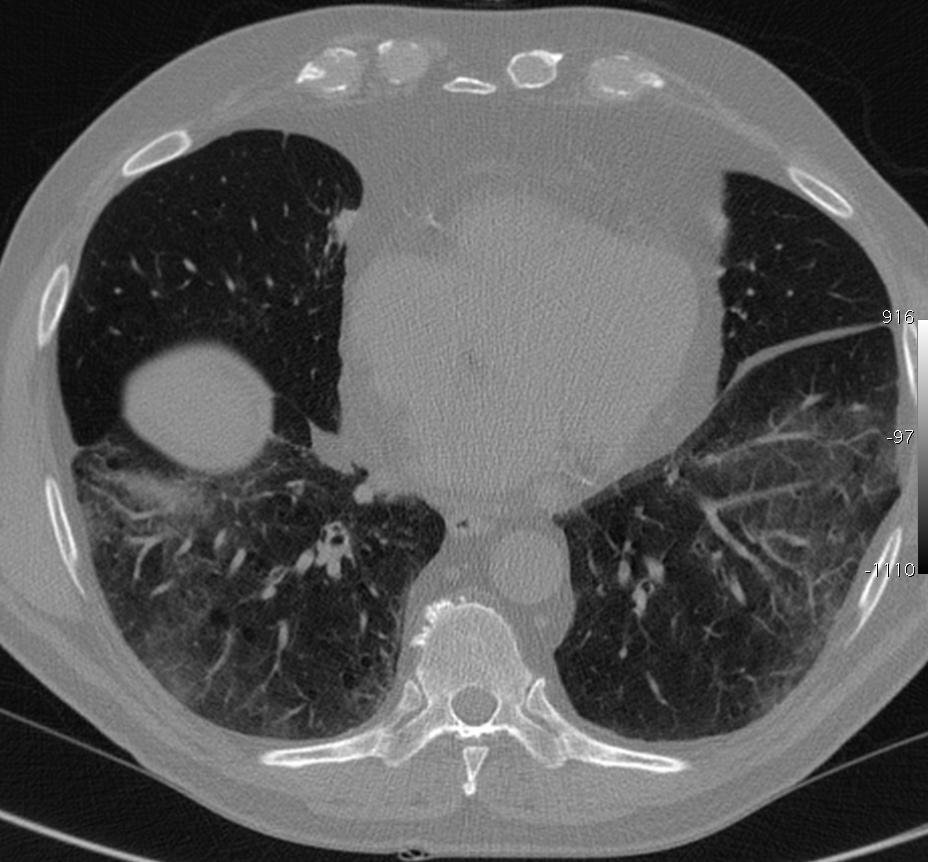

Foto por Mluisamtz11 (neumonía intersticial) – Own work, CC BY-SA 3.0.